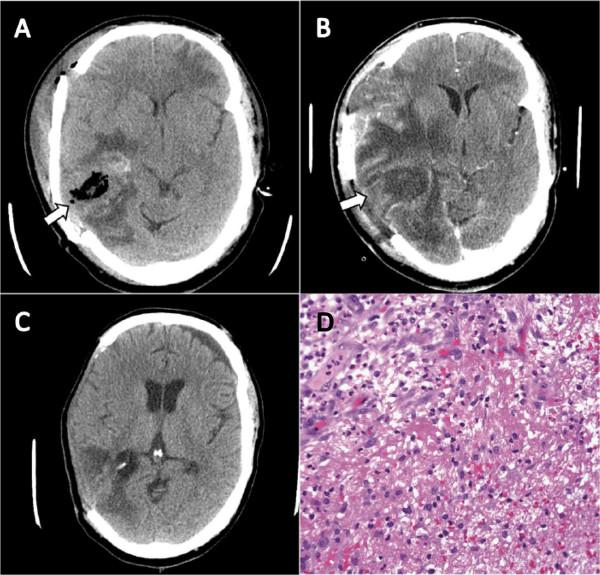

We report the case of a 40-year-old Somali man who sustained a traumatic brain injury that required initial neurosurgical hematoma evacuation and that subsequently was complicated by a hospital-acquired M. hominis brain abscess. Our patient was successfully treated with neurosurgical debridement and an antibiotic course of intravenous doxycycline.

我们报告一例40岁索马里男性病例,该患者因创伤性脑损伤接受了初期神经外科血肿清除术,随后并发医院获得性人型支原体脑脓肿。我们的患者通过神经外科清创术和静脉注射强力霉素的抗生素疗程成功治愈。